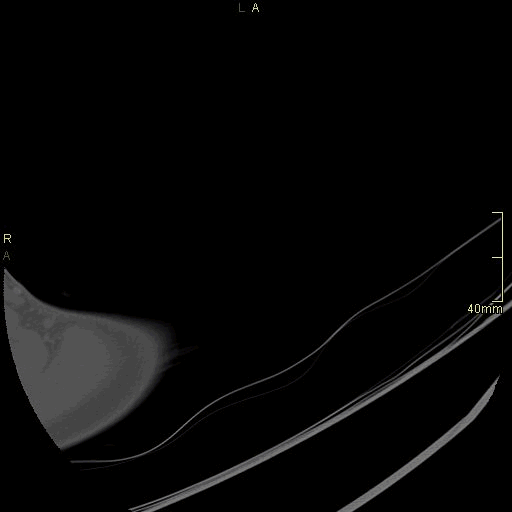

CT Humerus Non Contrast- Bone window (axial)

CT Humerus Non Contrast- Soft tissue window (axial)